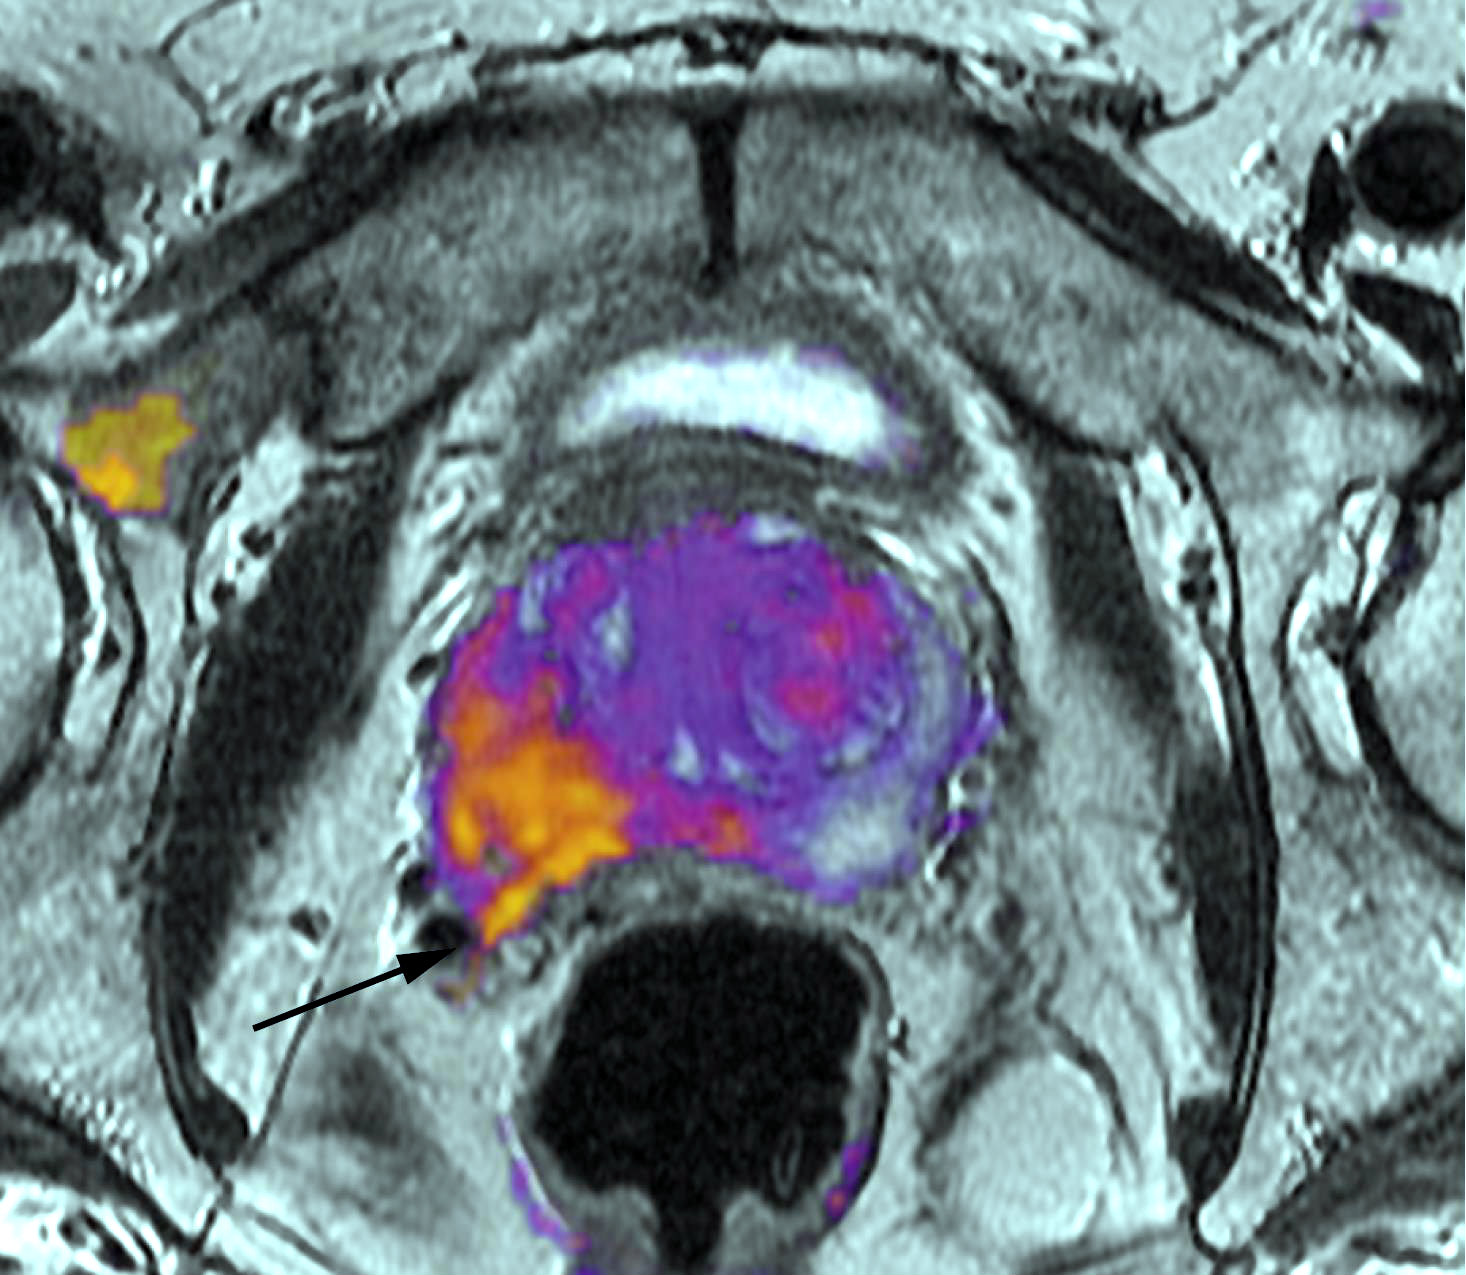

Diagnóstico y tratamiento del cáncer de próstata. Una revisión

29 junio 2017

JAMA, 28 de junio de 2017 Los avances en el diagnóstico y tratamiento del cáncer de próstata han mejorado la capacidad de estratificar a los pacientes por riesgo y han permitido a los médicos recomendar la terapia basada en el pronóstico del cáncer y la preferencia del paciente. El tratamiento inicial con quimioterapia puede mejorar la supervivencia en comparación con la terapia de privación de andrógenos